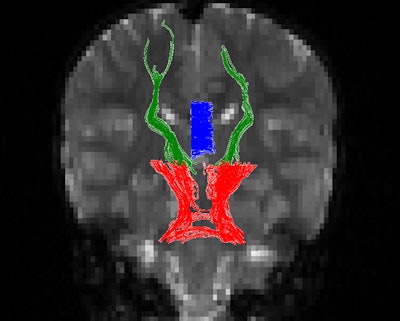

Diffusion-tensor MRI was performed on a 3-tesla scanner (Magnetom Trio, Skyra, or Verio, Siemens Healthcare) to assess white-matter tracts for the number of fiber trajectories, as well as tract volume and density, fractional anisotropy, and other measures.

The researchers found statistically significant differences in fractional anisotropy between the two groups, with the differences varying by three brain regions: the cerebellothalamic tracts, which are associated with working memory; the corpus callosum, which is associated with processing speed and IQ; and the thalamocortical tracts.